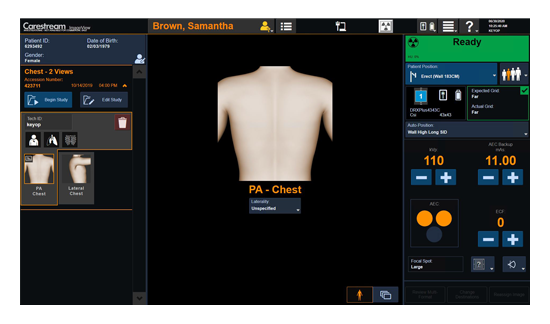

工作流智能。

在这里,先进的智能功能自动执行手动任务和工作流程步骤,以简化流程,提高技术人员工作效率,节省时间和金钱,并增强患者护理。

自动化设备定位和患者姿势确认可优化放射科技师的效率并加快工作流程。

自动技术选择可改善影像一致性并支持辐射剂量控制。

通过任务自动化功能改进感染控制,使放射科技师不再与潜在感染患者直接接触。

单屏工作效率与安全

ImageView 软件平台旨在通过提供以下功能,大幅提高影像效率和安全性:

所有 Carestream 影像采集产品通用的用户界面

减少屏幕切换,节省时间并增强工作流程

内置“安全设计”元素,提供入侵保护和防护